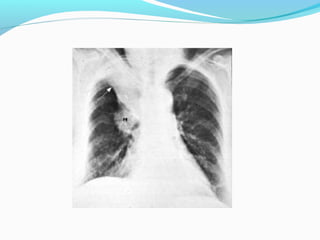

STAGE ??